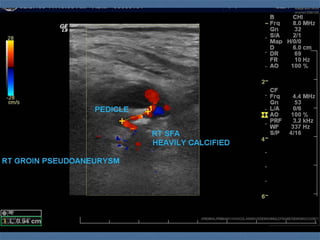

 Pseudoaneurysm

 Hematoma in continuity with lumen

 Dx: pulsatile mass; bruit; Duplex U/S

 All but the smallest (<2 cm) tend to rupture

 Rx: Vascular Surgery

 U/S guided compression of narrow neck (30 -60 min)

 Inject with procoagulants/coils